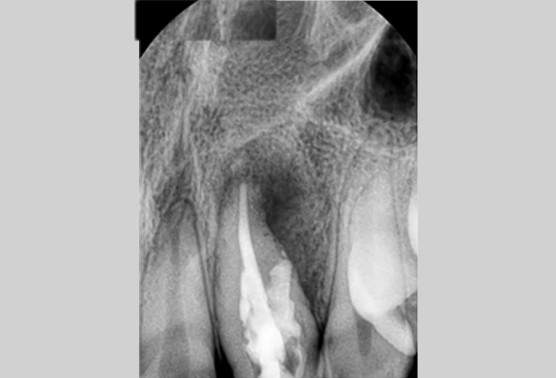

[치아만큼 큰 사이즈의 염증]

염증의 크기는 보시다시피, 치아만한 사이즈로 상당히 크게 자리를 잡고 있었습니다.

크기도 크기지만 위치가 치아 뿌리끝이 아닌 옆쪽으로 자리를 잡고 있습니다.

신경치료의 단순염증은 아니라는거죠.

보존과선생님의 진단으로는 치내치 및 구개측 천공으로 치근단절제술도 불가하고

소독을 계속해도 호전되지 않아 발치를 하기로 했다합니다.